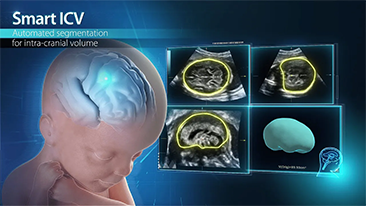

Optimierte OBG-Workflows sind n?tig, wenn gro?e Patientinnenzahlen im Rahmen von Gesundheitsscreenings bew?ltigt werden sollen. Zum Beispiel sind Fehlbildungen des zentralen Nervensystems (ZNS) eine der h?ufigsten angeborenen Anomalien. Wegen verschiedener f├╝r die Bildgebung ung├╝nstiger Bedingungen, etwa eine schwierige Position des F?tus, ist es besonders schwer, die MSP von 2D-Ultraschall zu erhalten. Aus diesem Grund k?nnen automatisierte Erkennung und Messungen die Scanning-Effizienz deutlich steigern.